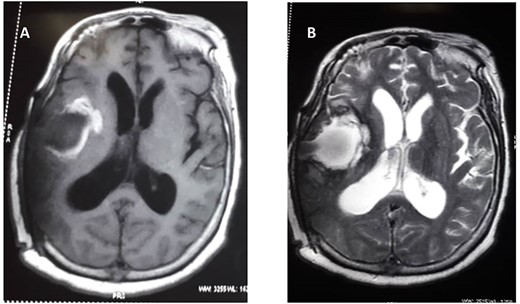

She subsequently had right frontotemporal craniotomy and tumour excision. Intraoperative findings were those of a mixed consistency mass, which was firm, gritty with areas of necrosis and brown coloured cystic components. Histopathological examination of the tumour revealed neoplastic papillary structures infiltrating a dense fibro-collagenous matrix. The neoplastic papillae showed discohesive cells lining delicate fibrovascular cores; the cells exhibited marked nuclear pleomorphism with hyperchromatic and vesicular nuclei. Some abnormal mitotic figures were also seen and there were no residual neural tissues present (Fig. 2A–C). The overall histopathological features were consistent with papillary meningioma (World Health Organization Grade III). The MRI at 3 months post-operative showed gross total tumour resection with an area of cystic cavitation because of encephalomalacia from the previous tumour and surgery (Fig. 3A and B). She subsequently had adjuvant radiotherapy and was lost to follow-up.

(A) Preoperative T1 weight. (B) T2-weighted MRIs. (C) Preoperative magnetic resonance spectroscopy.